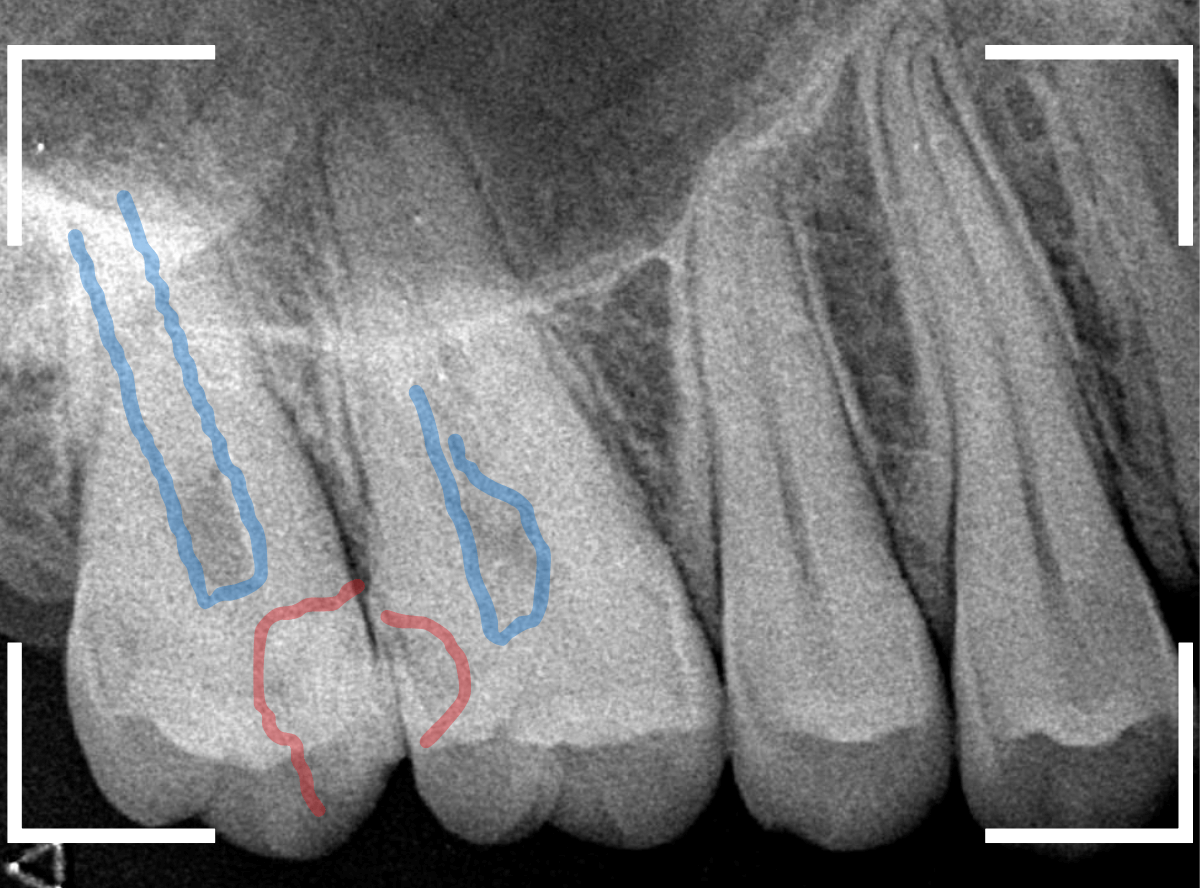

レントゲン写真で確認します。

赤い線が虫歯、青い線が歯の神経です。

歯のすきまから両側に虫歯が大きく広がっているのが確認できます。